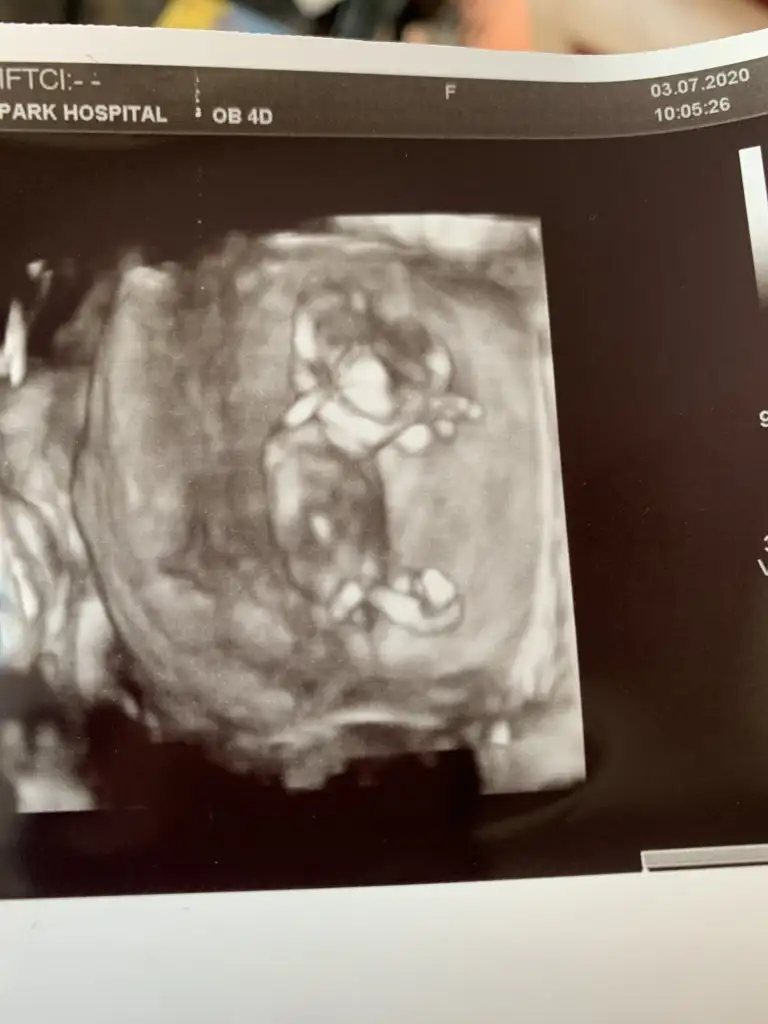

Merhaba cinsiyeti nedir sizce